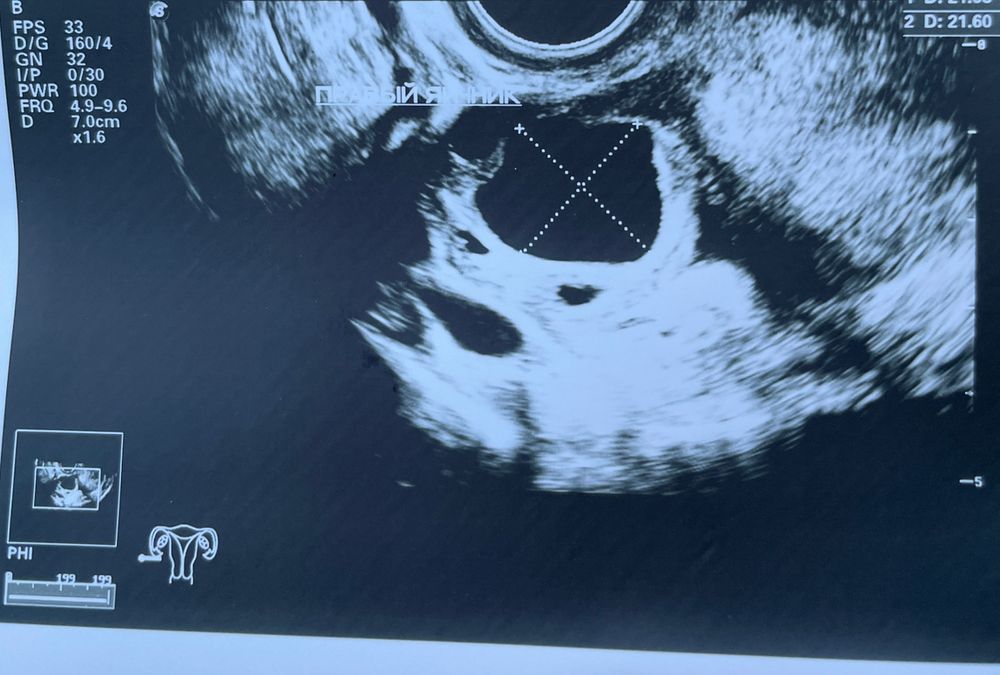

Узи через 25 дней (3 фото) - в заключении киста ЖТ с единичными кровотоками

Получается, при положительном тесте на овуляцию и болях - овуляция не произошла и фолликул снова не смог лопнуть самостоятельно и перерос в кисту?

Или же все таки совулировал и после выдал кистозное ЖТ?

Желтоеу тело появляется после овуляции, к тому же жидкость была.

скорее всего овуляция была, после желтое тело, которое и переросло в кисту.